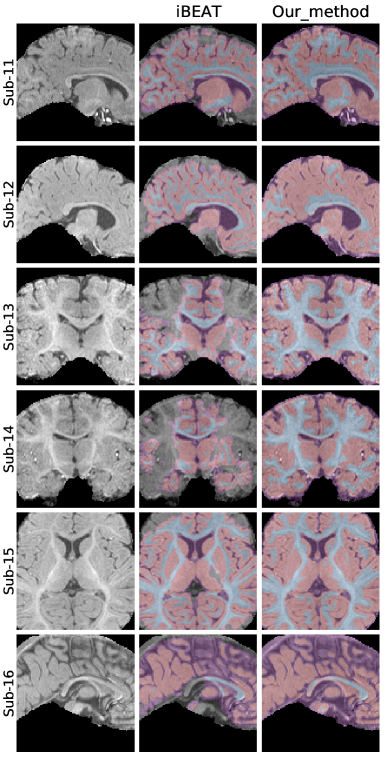

5.2 Qualitative comparisons on raw infant data

To provide a clear visual assessment of segmentation performance, we present a diverse set of qualitative results obtained using different methods. Figs 4 and 5 illustrate a side-by-side comparison between the competing approaches and the silver-standard ground truth generated by Infant FreeSurfer. Specifically, we highlight the 30 most discordant MRI volumes, identified as those exhibiting the highest variance in DICE scores across the evaluated methods when compared to Infant FreeSurfer segmentations. By focusing on these challenging cases, we enhance the visibility of key differences in anatomical structure delineation, allowing for a more insightful comparison of method effectiveness.

This visualization strategy ensures that performance disparities between compared approaches are clearly distinguishable, providing an intuitive and informative perspective on the strengths and limitations of each method, including our proposed solution.